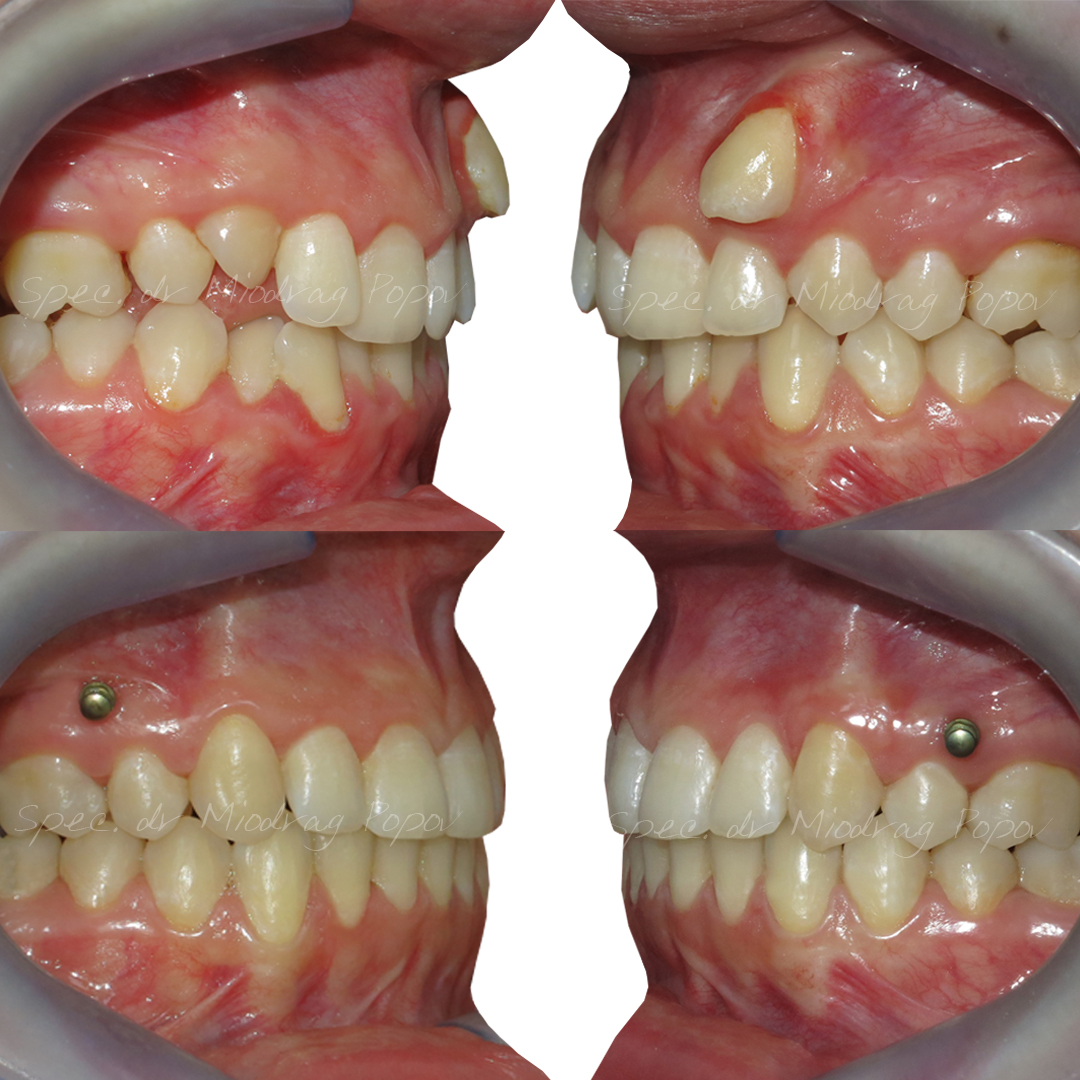

Danas predstavljamo slučaj gde je ektopično, bukalno postavljen očnjak – vidljiv pri osmehu, uspešno vraćen u zubni niz.

Bitno je istaći da je uz precizno vođenu mehaniku i upotrebu konzole i mini implantata, postignut fenomenalan estetski rezultat.

Pacijentkinjin profil je ostao nepromenjen, dok je osmeh postao još lepši i prirodniji!